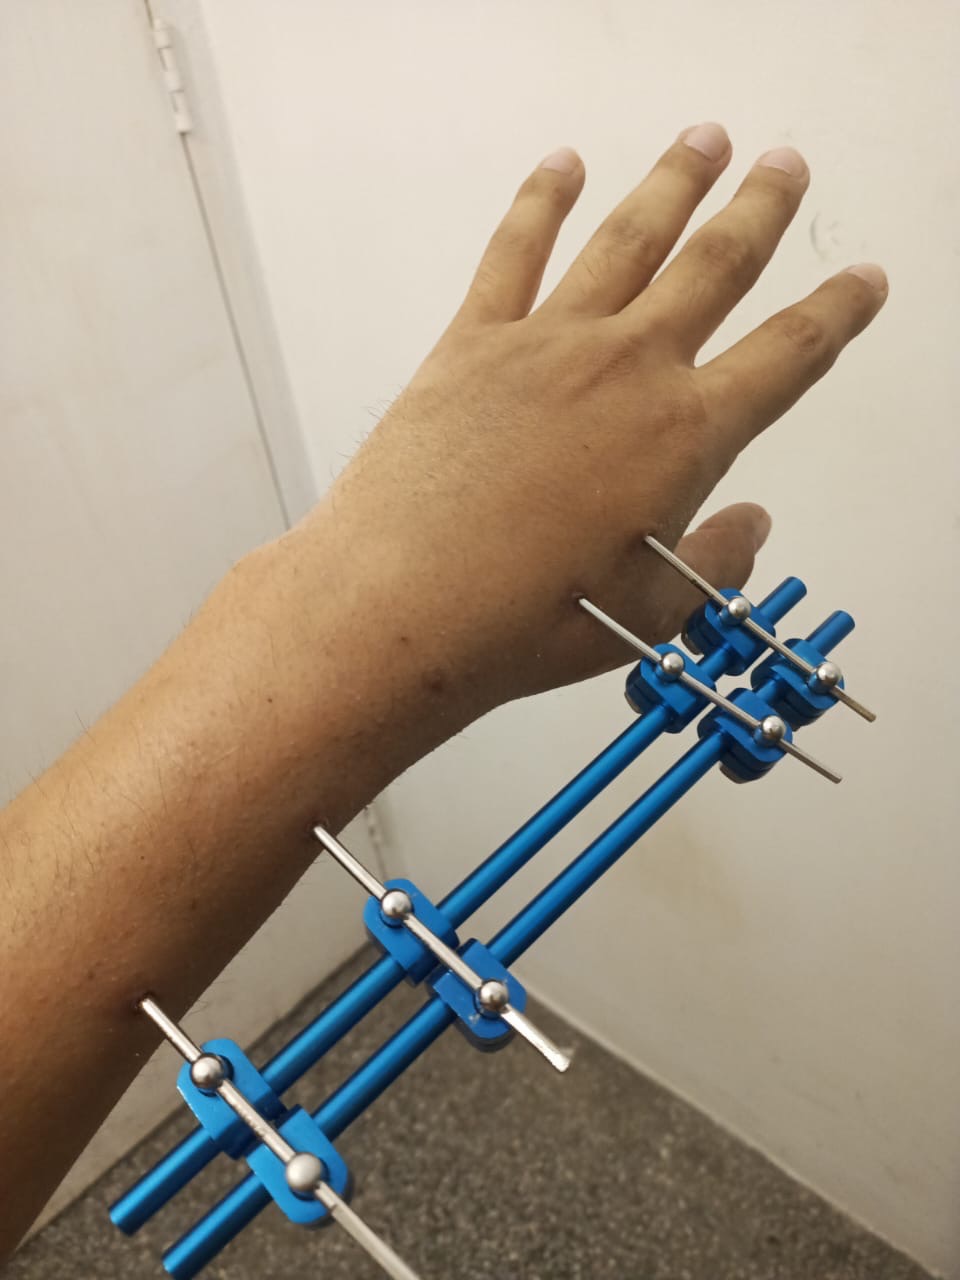

Los médicos determinaron que necesitaba un soporte más firme. En una segunda operación, le colocaron una placa DVR y un tutor externo. Cada tornillo representaba una esperanza de volver a utilizar su muñeca izquierda para generar ingresos para su familia, pero sus huesos al no tener el uso cotidiano que normalmente sostenían no respondieron como esperaban. La placa, aunque era una buena posibilidad de solucionar la lesión, no resultó.

Recientemente, Simón enfrentará su tercera cirugía: el retiro de la placa y el tutor. Esto con el objetivo de posible rehabilitación para darle movimiento los músculos y demás articulaciones evitando que se atrofien y adicionalmente realizarse una tomografía para evaluar el siguiente paso a seguir. Los médicos hablan de una cuarta operación, más compleja y costosa, que podría ser su última oportunidad para recuperar la movilidad completa de su mano.